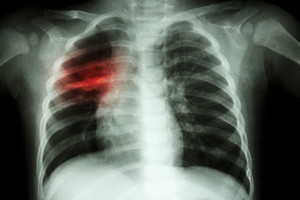

Higienos instituto duomenimis, 2016 m. piktybiniai navikai buvo antra pagal dažnumą mirties priežastis šalyje. Nuo jų praėjusiais metais mirė 17,7 proc. moterų – daugiausia dėl krūties, storosios žarnos ir kiaušidžių piktybinių navikų, ir 22,3 proc. vyrų – daugiausia dėl trachėjos, bronchų, plaučių ir prostatos onkologinių ligų. Nuo kraujotakos sistemos ligų, kurios buvo pirma pagal dažnumą mirties priežastis šalyje, mirė 64,4 proc. moterų ir 47,8 proc. vyrų.

„Šalyje ne tik didėja sergančiųjų kritinėmis ligomis skaičius, bet ir jaunėja amžius. Išmokas už onkologines ligas išmokame nė trisdešimties nesulaukusiems savo klientams. Tokia statistika verčia susimąstyti, pagalvoti apie save. Gyvybės draudimas negali apsaugoti nuo sunkios ligos, tačiau išmoka, gauta susirgus, gali padėti kovoti su liga, rinktis efektyvų gydymą ir reabilitaciją“, – sako „Aviva Lietuva“ vyr. draudimo rizikos vertintojas, gydytojas Šarūnas Žemaitis.